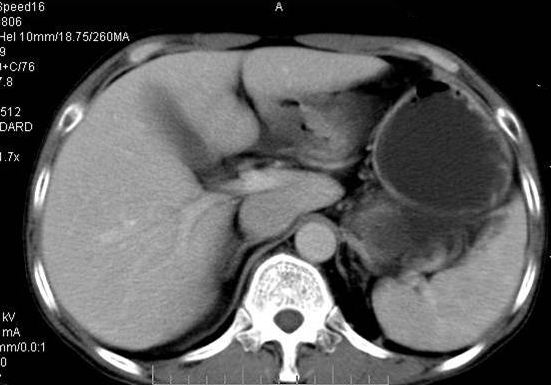

右侧多发性肾囊肿,其中之一巨大(不排除其为重复肾积水可能);右肾积水。

考虑右肾多发囊肿并出血

囊性肾癌可能性大,右肾多发囊肿。

定位;肾明显与病灶杯口相交,可以肯定病变来自右肾。

定性;病灶囊性为主,前下部含实性成分,及钙化,部分壁厚薄不均。

综上考虑;囊性肾癌》重复肾伴积水。